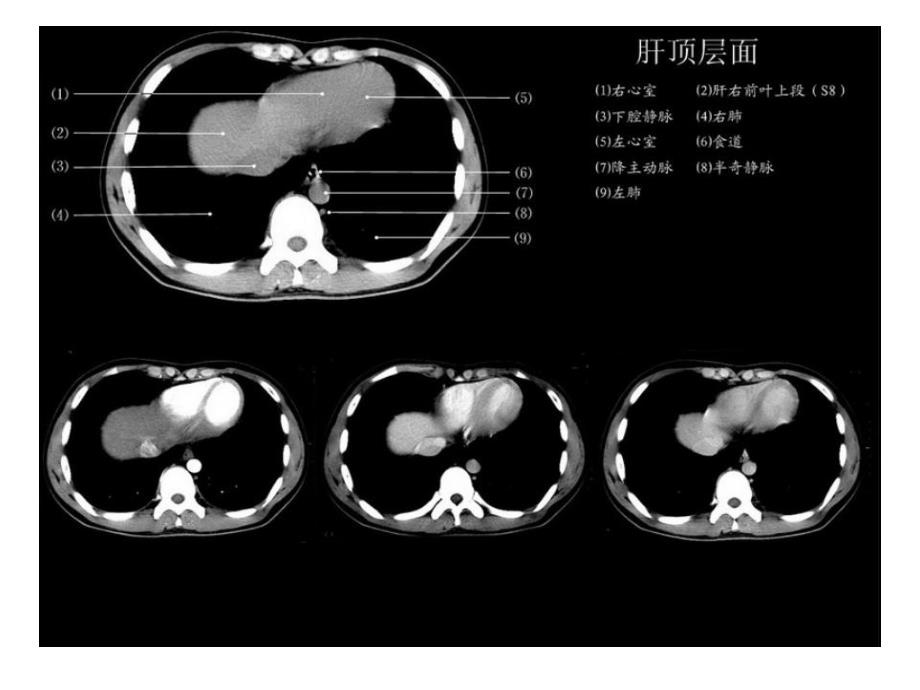

正常肝脏正常肝脏CT解剖解剖